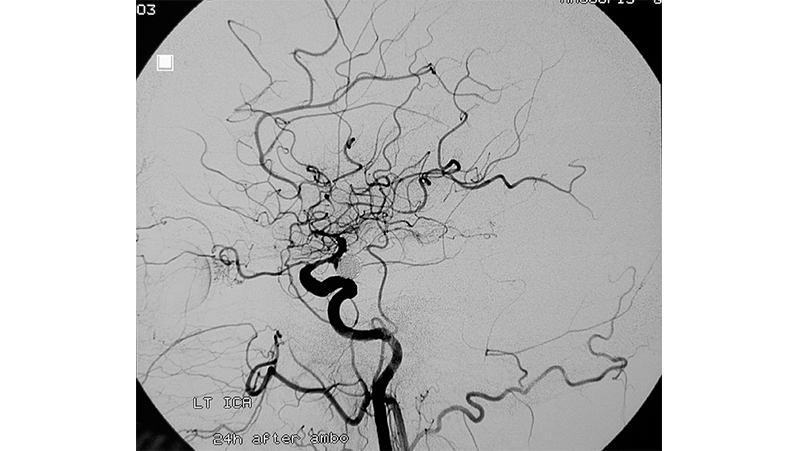

Εικόνα 3: 24 ώρες αργότερα η ασθενής επιβαρύνθηκε κλινικά και διασωληνώθηκε εκ νέου λόγω πτώσεως του επιπέδου συνειδήσεως. Σε νέο αγγειογραφικό έλεγχο βλέπουμε την υποτροπή του αγγειοσπάσμου με ελαττωση της παρεγχυματογραφίας του αριστερού ημισφαιρίου.